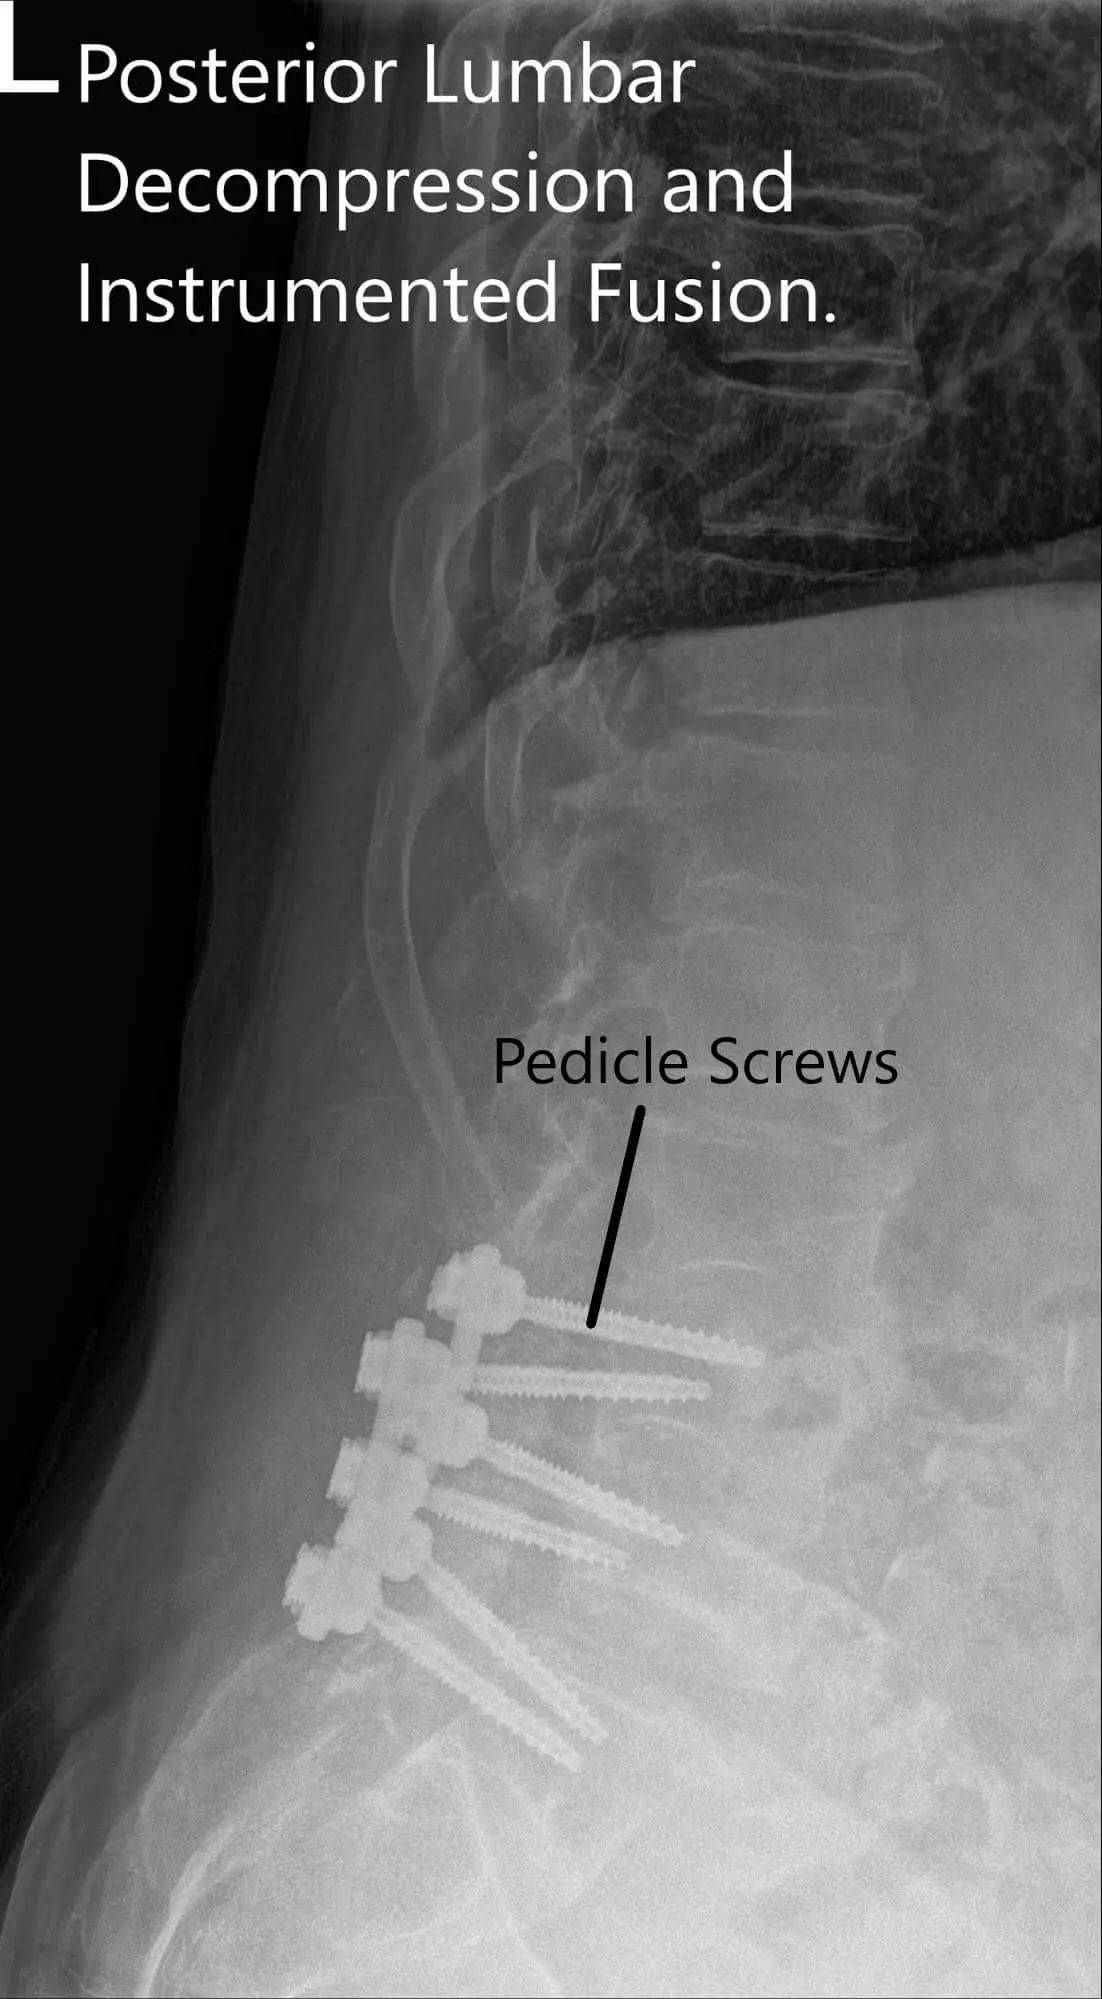

Postoperative X-ray showing AP and Lateral Views.

Now the pedicle screws for the S1 were planned and the pedicle of S1 was probed from either side and checked under C-arm. After finding an acceptable position. The pedicle screw of 6 mm x 45 mm cortical fix screw was put on both pedicles of S1.

The pedicles of L5 were cannulated now and the position of the probe was checked under the C-arm and found to be acceptable and biopsy material was sucked out using a Jamshidi needle from the right pedicle of LS. Some tissue and bone marrow aspirate was sent for biopsy. A 6 mm x 40 mm cortical fix screw was inserted on both pedicles of L5.

The pedicles of L4 were cannulated similarly and checked under C-arm and found to be acceptable. A 6 mm x 45 mm cortical fix screw was inserted on both pedicles of L4. The screw heads were lined well on both sides. The wound was washed copiously with normal saline mixed with Bacitracin and gentamicin.

The screws were lined and rods were placed on both sides and tightened to the screw heads. The final pictures of the screw were taken with C-arm and saved. Hemostasis was achieved. Vancomycin antibiotic was sprinkled into the wound. Considering the durotomy a deep suction drain was not put. The closure was done in layers. Two suprafascial drains were put. The counts were completed, checked, and correct at the end of the procedure. The patient was transferred into a supine position on the bed, extubated, and moved to the postoperative care unit in a stable condition.